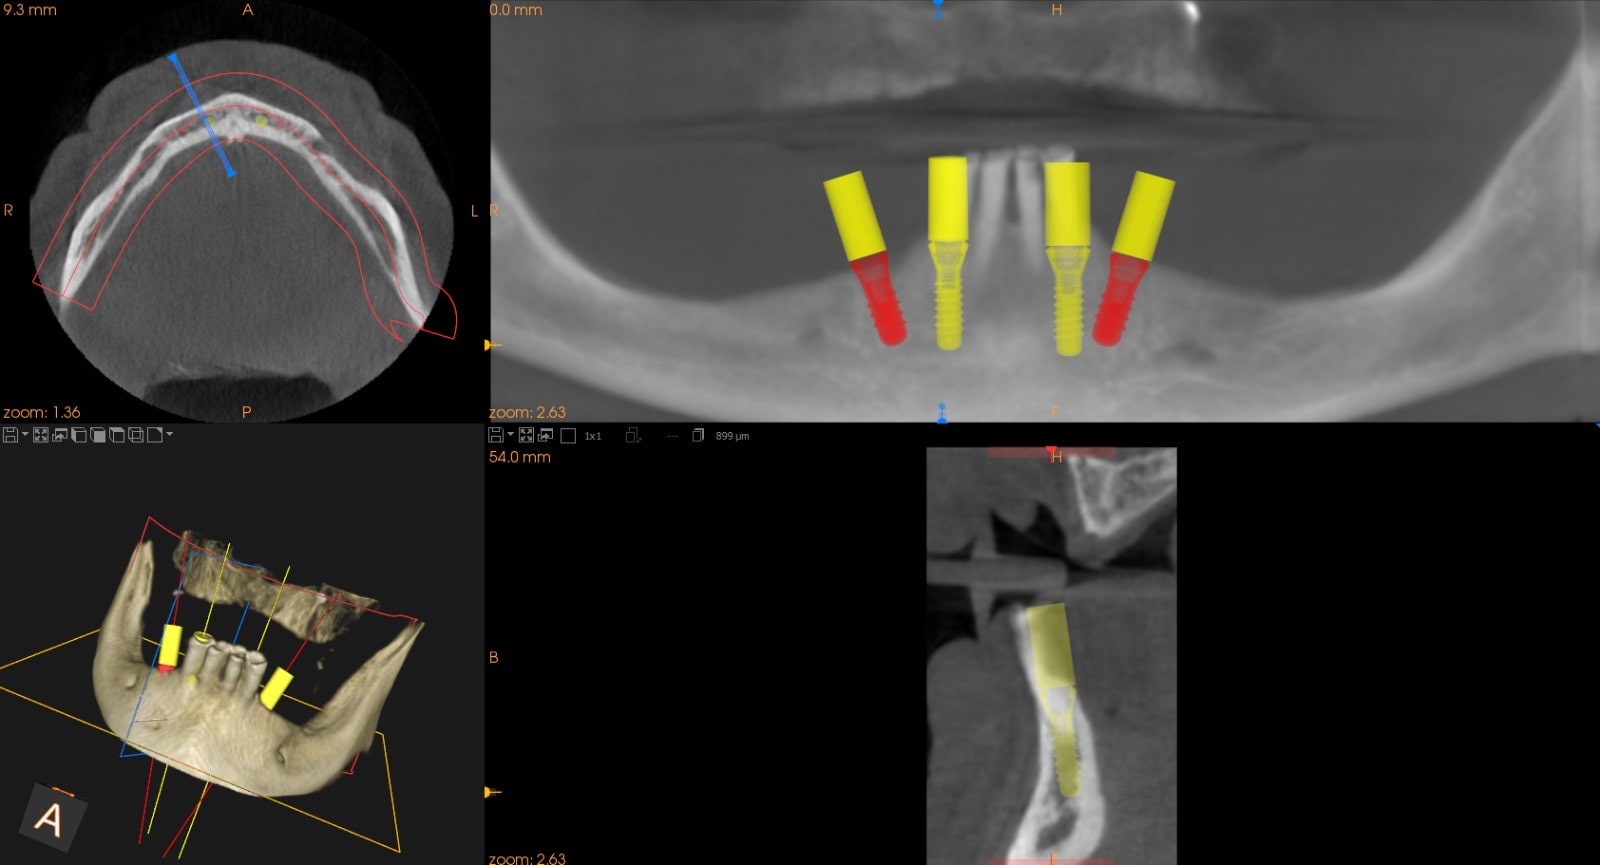

Pianificazione digitale e chirurgia guidata

CBCT e pianificazione digitale per chirurgia guidata

Ogni intervento implantare è preceduto da un’accurata pianificazione digitale:

• utilizziamo esami radiologici 3D (CBCT),

• elaboriamo modelli virtuali,

• valutiamo posizione, inclinazione e profondità dell’impianto in relazione ai tessuti duri e molli.

Questa sinergia di tecnologie consente di trasformare la fase chirurgica in un atto estremamente controllato, sicuro e predicibile, garantendo risultati eccellenti sia dal punto di vista funzionale che estetico.